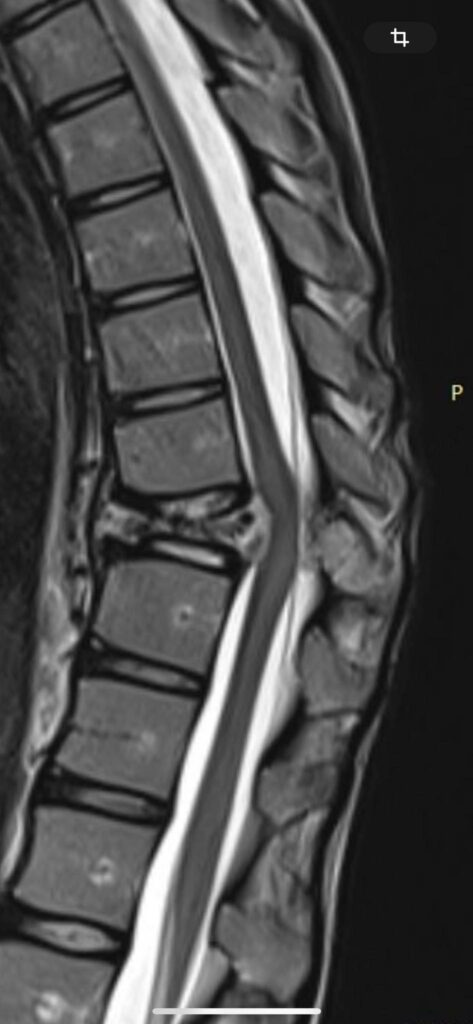

У дівчини, яка навчається в 10-му класі місцевого ліцею №1, діагностували пухлину грудного відділу хребта, повідомляє у Facebook Світлана Киричук.

Станом на зараз утворення вже почало стискати спинний мозок, що створює пряму загрозу здоров’ю дитини. Аделіна потребує термінової дороговартісної операції, яка дозволить їй позбутися болю та повернутися до нормального життя.